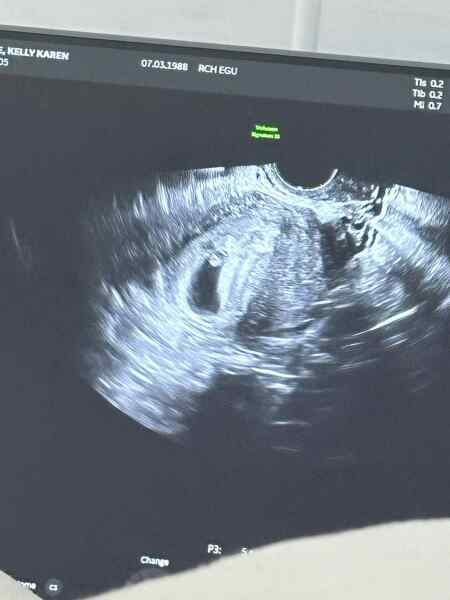

Just for fun really as I know it’s 50/50 but anybody any good at guessing this haha? Transvaginal scan. 7 weeks 5 days but measuring 6 weeks 6 days at the time of the scan 🤍 thank you xx